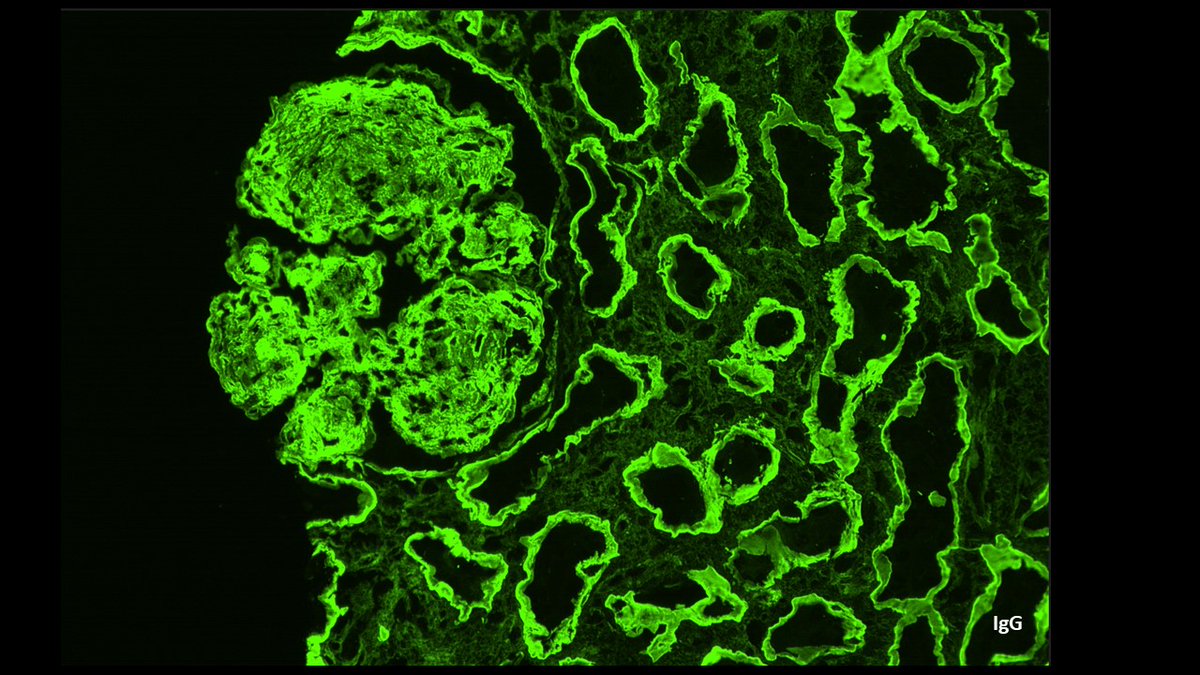

Diagnosis unmasked. Young F with 2g proteinuria, weak +dsDNA. Membranous pattern, IF with C3 dominant staining. Pronase IF --> IgG-k. Membranous-like glomerulopathy with masked monotypic IgG-k deposits. Considered to be autoimmune; not MGRS. #renalpath #pathtwitter #nephrology.